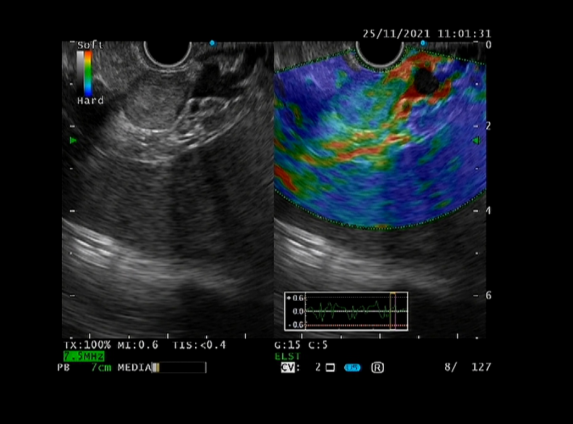

EUS—消化内镜领域的“第三只眼”

超声内镜(EUS)是将内镜和超声相结合的消化道检查技术,将微型高频超声探头安置在内镜顶端,当内镜插入体腔后,在内镜直接观察消化道黏膜病变的同时,可利用内镜下的超声行实时扫描,可以获得胃肠道的层次结构的组织学特征及周围邻近脏器的超声图像,从而进一步提高内镜和超声的诊断水平。